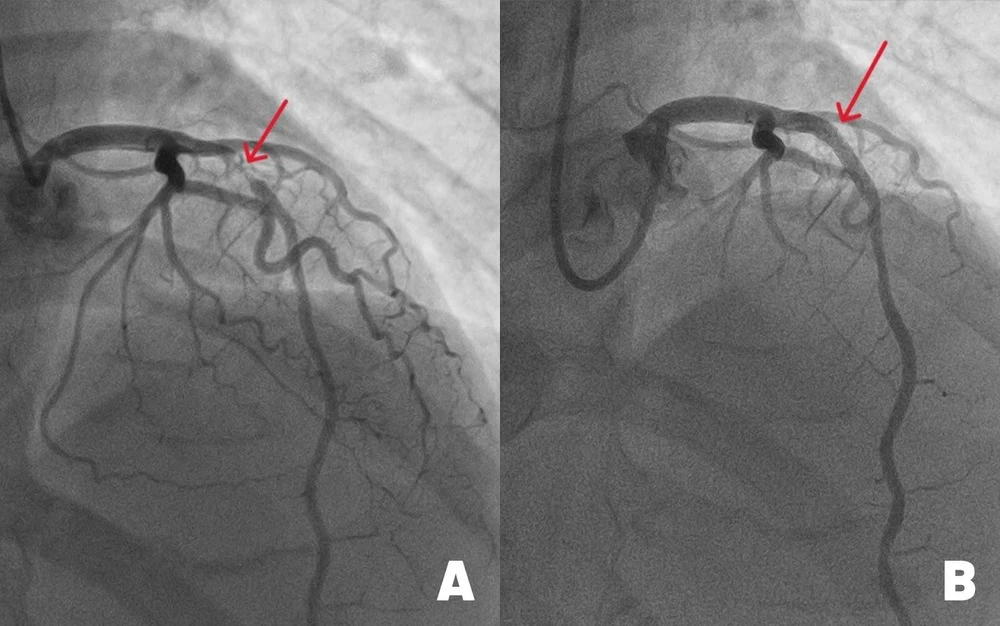

Hình ảnh động mạch liên thất trước (mạch máu chính nuôi tim) bị đứt do tắc nghẽn nặng (hình A) và sau khi được tái thông nhờ đặt stent kích thước lớn. Ảnh: BVĐK Tâm Anh |

Kết quả chụp mạch vành cho thấy, động mạch liên thất trước hẹp đến 99%. May mắn là vẫn có một dòng chảy nhỏ giúp cầm cự, tưới máu tạm thời nuôi cơ tim. “Với tình trạng này, cần can thiệp đặt stent càng sớm càng tốt cho bệnh nhân để tái thông dòng máu, tránh nguy cơ đột quỵ tim có thể xảy đến bất cứ lúc nào”, bác sĩ Long cho biết.

Với kinh nghiệm xử lý những ca hẹp nặng mạch vành, bác sĩ Long và êkip luồn ống thông từ động mạch quay (ở cổ tay) tới chỗ xuất phát động mạch vành trái. Sau đó, luồn sợi dẫn 0.35mm qua vị trí hẹp ở động mạch liên thất trước. Dưới sự hỗ trợ của hệ thống siêu âm trong lòng mạch (IVUS), êkip đo đạc chính xác đường kính mạch máu, đặt một stent phủ thuốc, nong nở rộng lên đến 4.0 mm, áp sát thành mạch, ngăn nội mạc mạch máu tăng sinh quá mức. Điều này giúp giảm nguy cơ tái hẹp trong stent, tái phát nhồi máu cơ tim xuống thấp (dưới 2%).